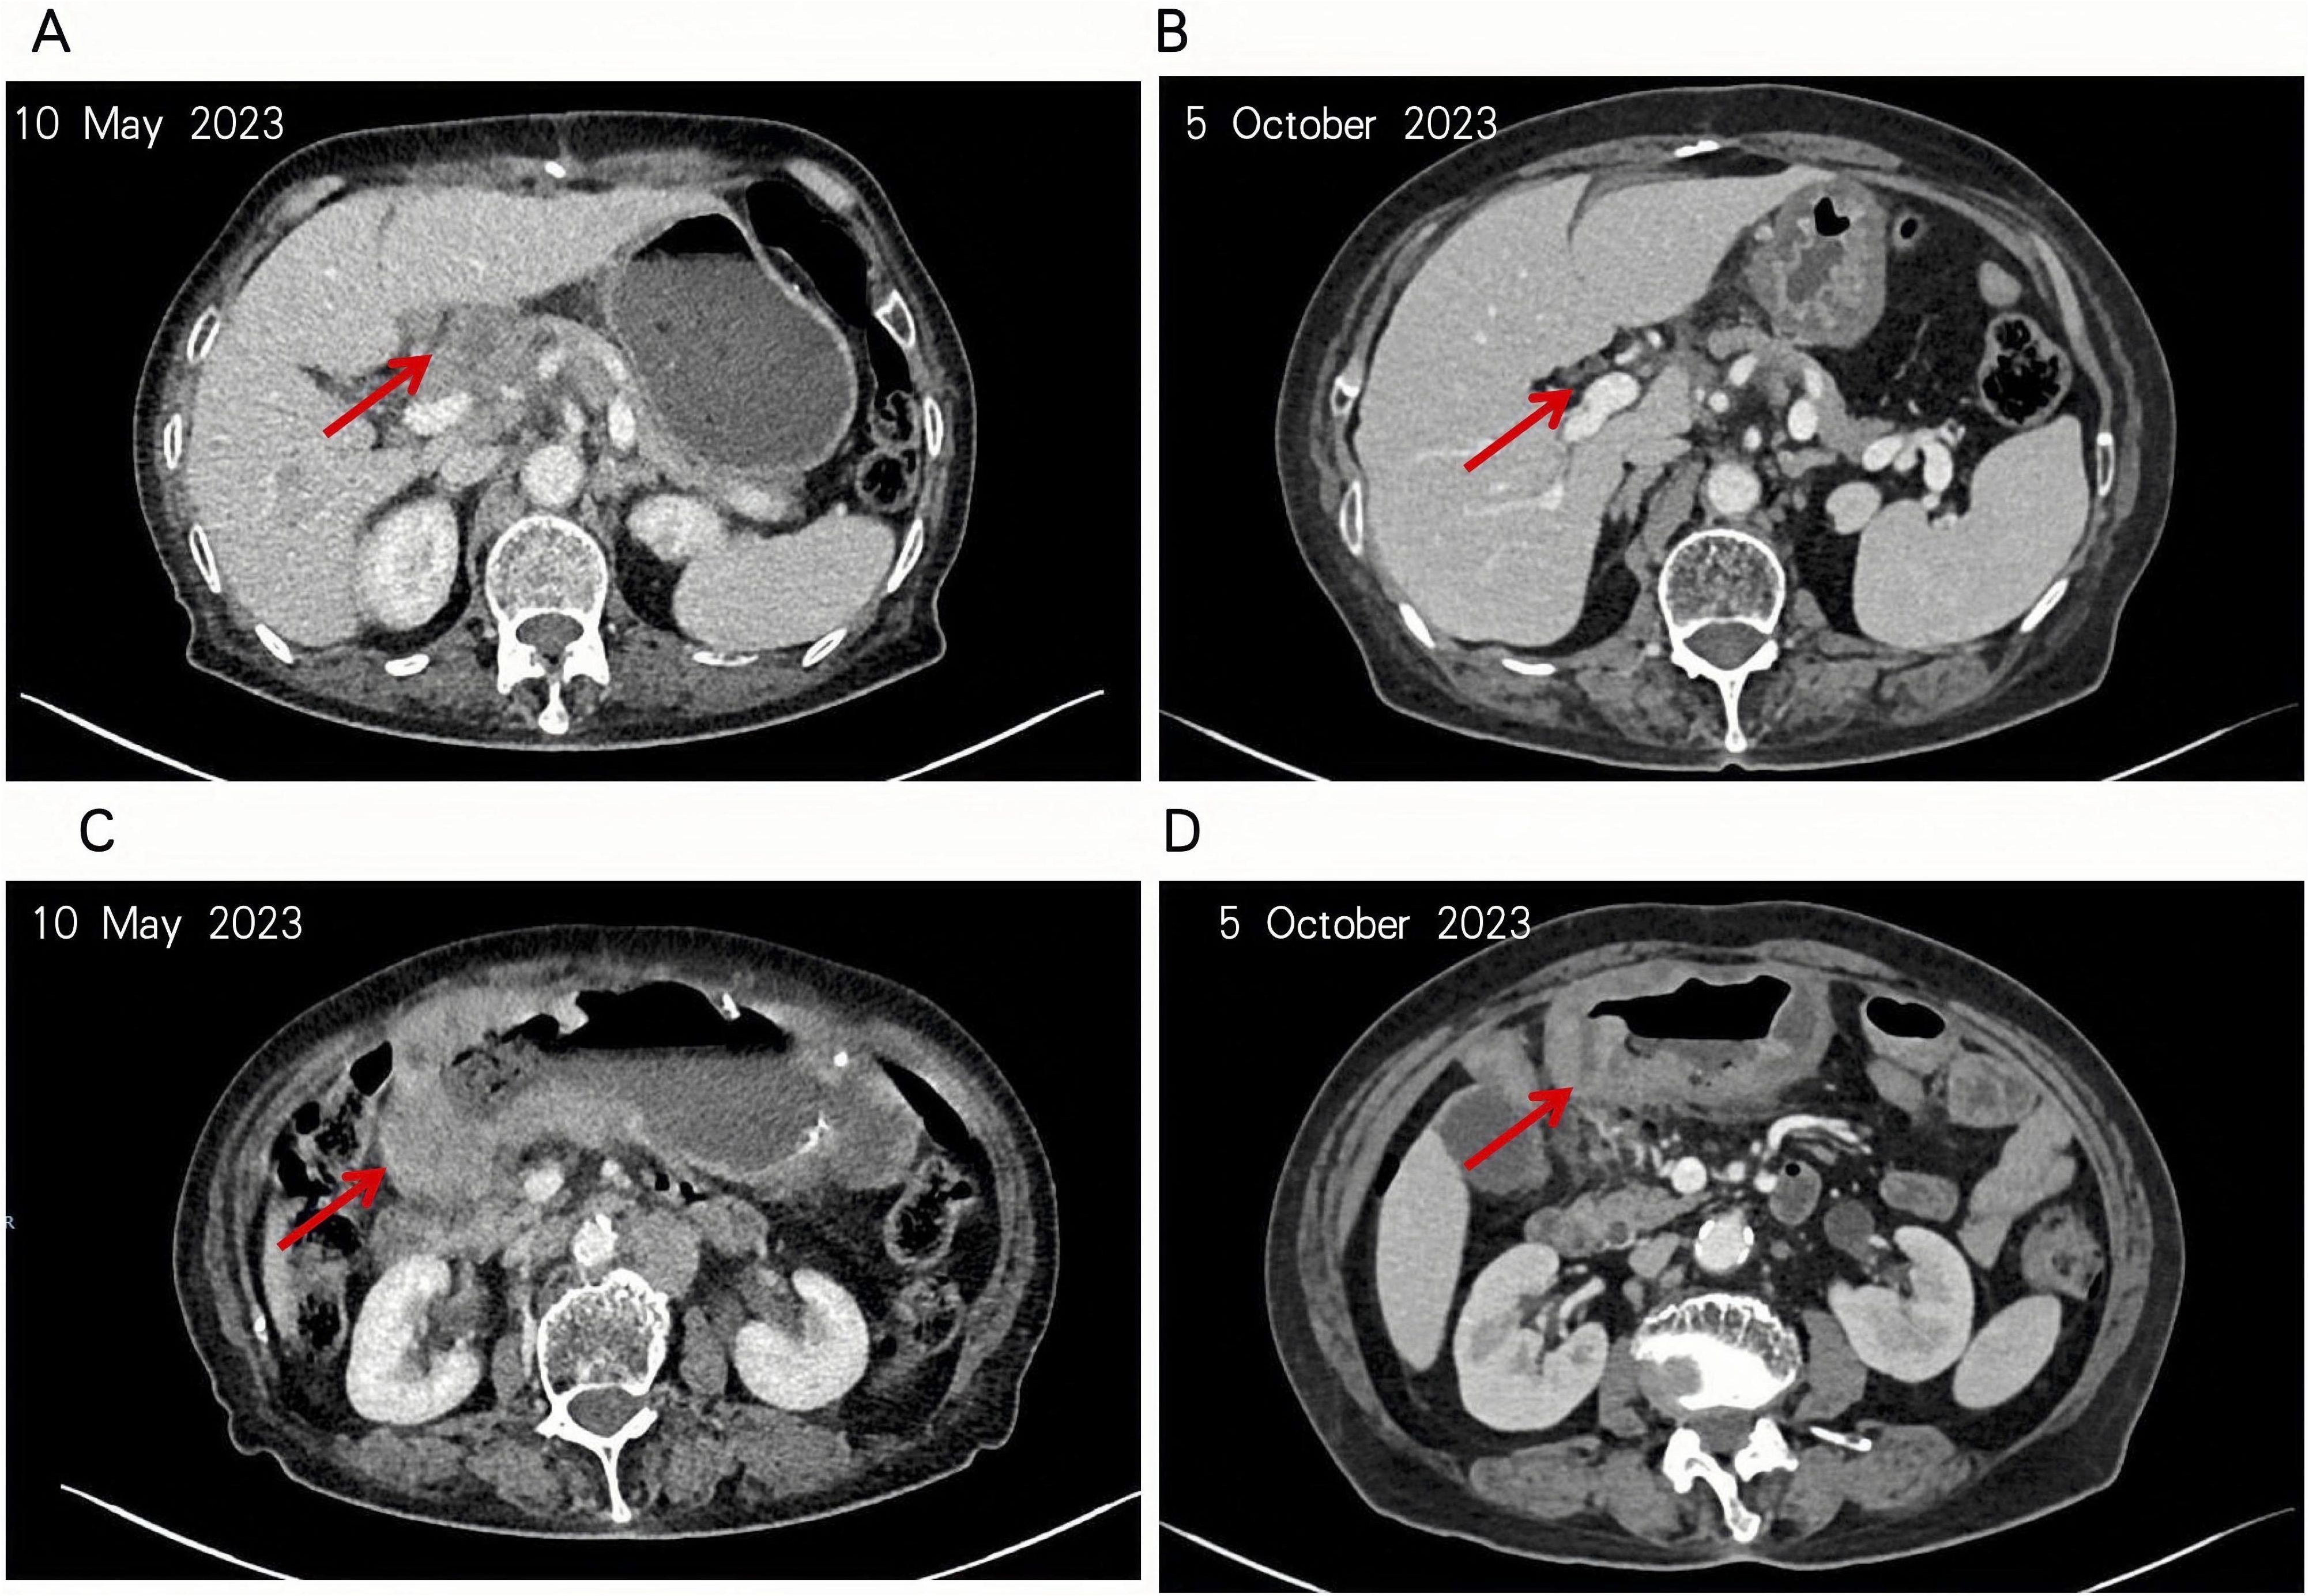

The patient initiated sintilimab on May 12, 2023, but treatment was complicated by severe declines in hemoglobin and platelet counts, leading to discontinuation and irregular continuation of immunotherapy. The first efficacy evaluation was conducted after completion of a single treatment cycle, approximately 4.5 months later. Cross-sectional imaging on October 5, 2023, revealed substantial regression of both the primary tumor and regional lymph nodes (Figure 3), consistent with a partial response (PR). However, disease progression was documented on November 28, 2023, and therapy was switched to cadonilimab. Imaging on January 26, 2024, again showed PR, followed by stable disease on March 20 and April 3, 2024. Nevertheless, by September 10, 2024, radiographic assessment confirmed progression, prompting initiation of ivonescimab therapy.

Figure 3

Four abdominal CT scans in two rows compare images from May 10, 2023, and October 5, 2023. Red arrows indicate focal points in each image: A and C are from May showing certain features, while B and D from October highlight changes or progressions.

Figure 3. The patient’s tumor and hepatogastric interstitial lymph nodes were significantly reduced. (A, B) The patient’s lymph nodes in the hepatoportal and hepatogastric hiatus were significantly reduced as seen in the intravenous phase of enhanced CT. (C, D) Notable regression of the patient’s tumor in the gastric antrum observed in the same enhanced CT sequence.